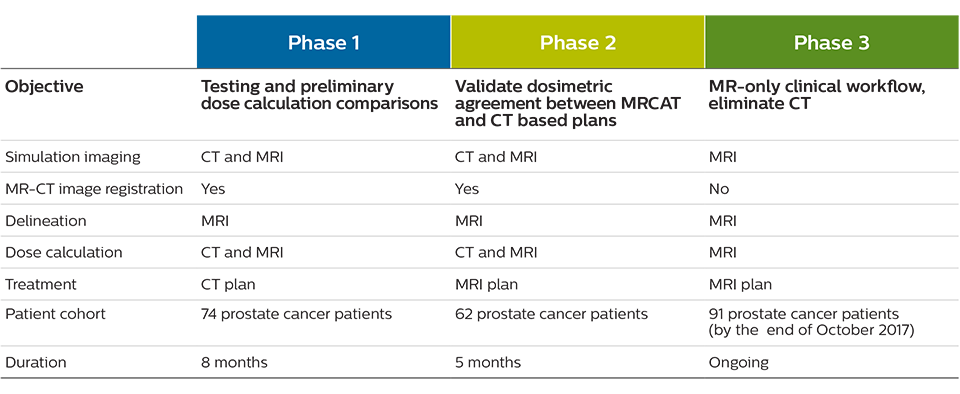

TYKS’s assistant chief physicist Jani Keyriläinen, PhD and medical physicists Sami Suilamo, Lic.Phil., and Pauliina Wright, PhD, led a three-phase commissioning process for MR-only simulation use in prostate radiotherapy, that began in January 2016 and concluded in March 2017. The first phase lasted eight months and consisted of CT-MRI simulation of a control group involving 74 prostate cancer patients.

“These first patients were planned based on CT simulation, but we also did preliminary dose calculation comparisons with both CT and MRI data sets,” Dr. Keyriläinen says. “In the second phase, October 2016 to February 2017, we imaged 62 patients with both CT and MRI, but these patients were planned with the MR images only.

We felt comfortable doing that because we were using thresholds in the dose calculation comparisons – for the planning treatment volumes PTV mean and PTV median – that were set to 2%. We very rarely went over 1% and the average difference in PTV mean values was 0.8% for all 62 patients in the dose comparison. In short, the dose differences between MRCAT- and CT- based radiotherapy plans were minimal. That was a really good sign for us to trust MR-only simulation in the third phase.”

“Since March 2017 we have been using MR-only simulation for our prostate patients routinely,” he says. “So all of the plans are based on MR imaging and calculations. Overall, the commissioning phase went smoothly. Because MR-only simulation is a commercial solution, the learning curve was short, which made commissioning much easier and faster. We didn’t have to start from scratch and find all of the tools ourselves.”

Three-phase commissioning process for MR-only simulation at TYKS